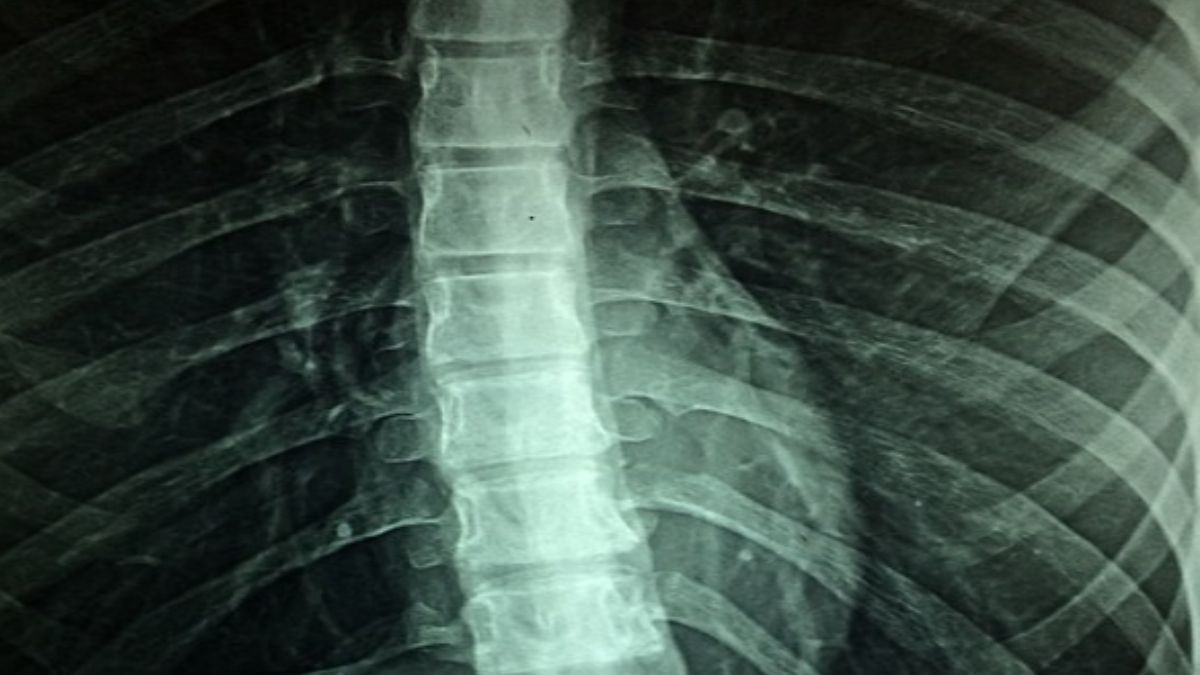

जिस तरह दिमाग में ब्लड की सप्लाई रुकने पर ब्रेन स्ट्रोक होता है, ठीक उसी तरह रीढ़ की हड्डी में अगर ब्लड सप्लाई किसी भी वजह से प्रभावित हो जाए, तो ये स्थिति स्पाइनल स्ट्रोक को जन्म देती है। ये ब्रेन स्ट्रोक की ही तरह बेहद खतरनाक होता है। ये जानलेवा भी हो सकता है।

जब रीढ़ की हड्डी में सही तरीके से खून का प्रवाह नहीं होता तो इसकी वजह से ऑक्सीजन सप्लाई भी बाधित हो जाती है। ऐसे में स्पाइनल स्ट्रोक के साथ-साथ स्पाइन कार्ड इंफ्रेक्शन की समस्या भी पैदा हो जाता है। ऐसे में सेल्स मर जाते हैं और इनके मरने पर हाथ पैरों का संचालन रुकने लगता है। इंसान को ऐसी स्थिति में लकवा भी मार सकता है।